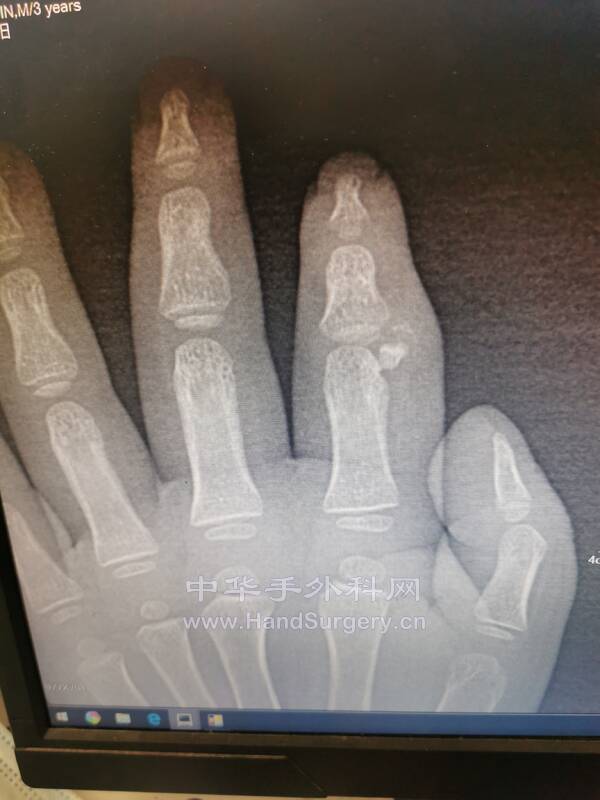

3岁儿童示指多指较少见

骨突切除,侧副韧带重建

术中见赘生骨突是长在侧副韧带深层的

应该进行侧副韧带紧缩缝合

不能应用可吸收钉在中节指骨基底部进行止点重建